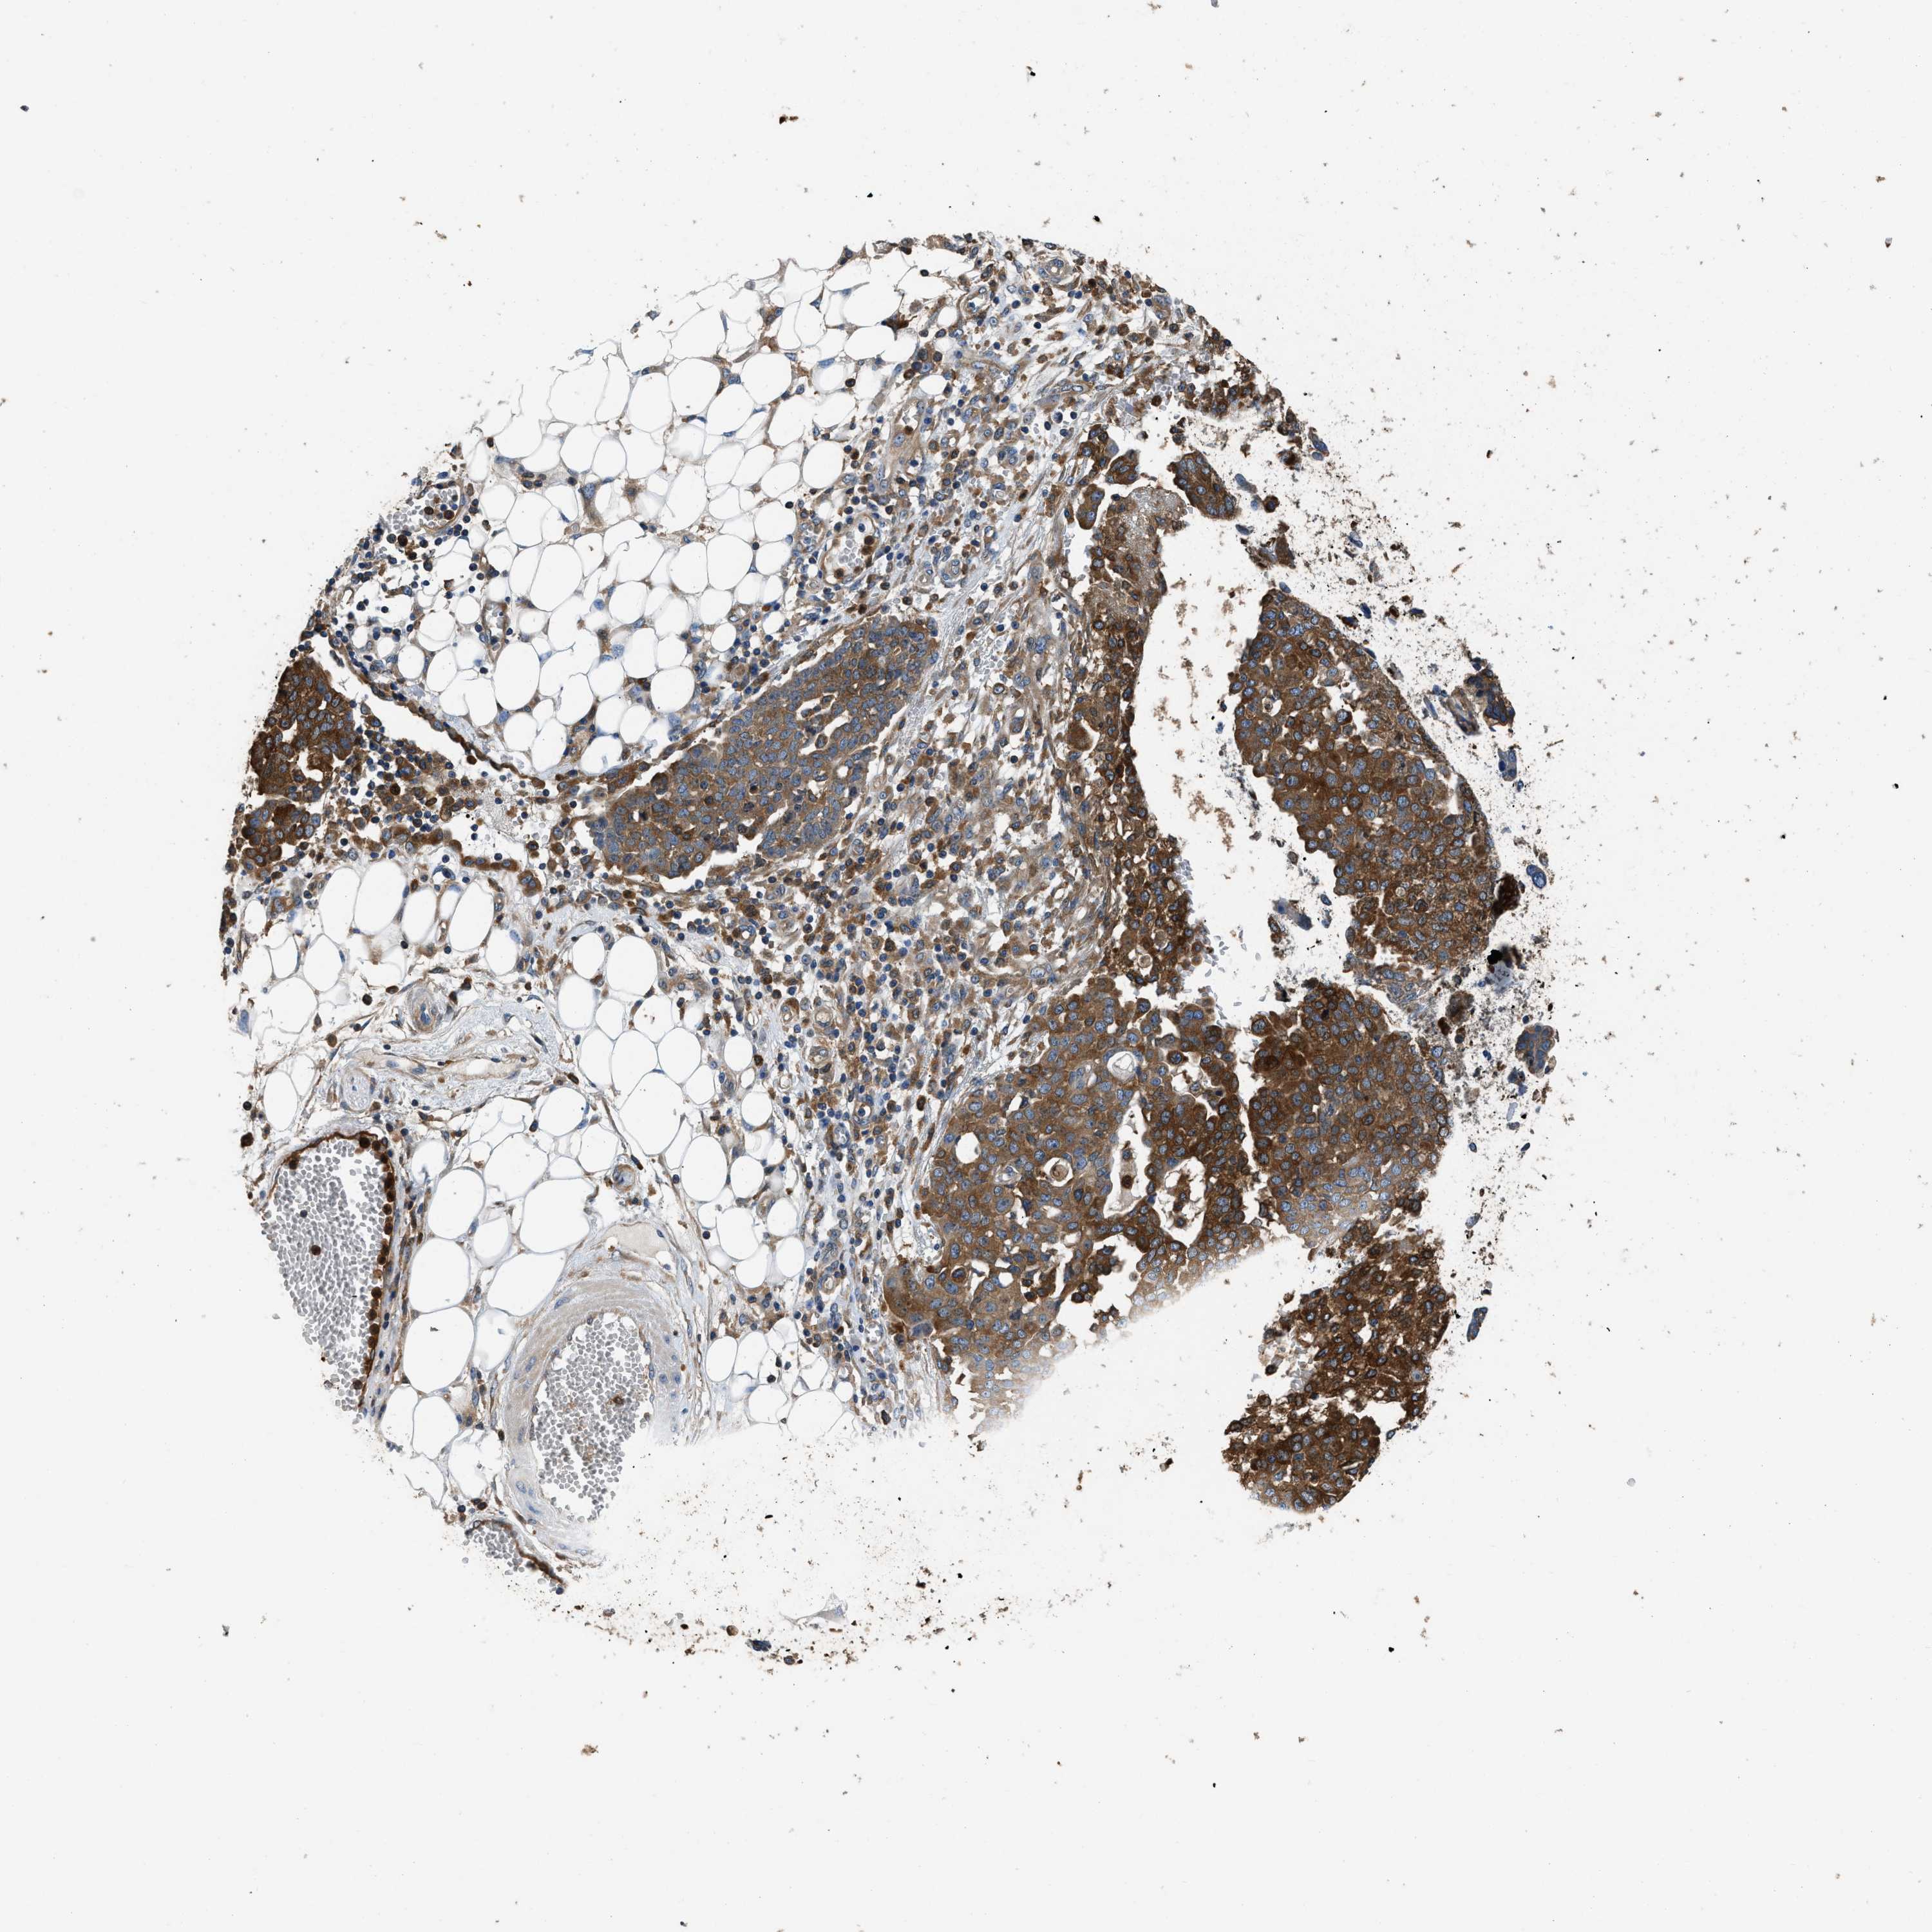

OVARIAN CANCER - Protein expressioni

A mouse-over function shows sample information and annotation data. Click on an image to view it in a full screen mode. Samples can be filtered based on level of antibody staining by selecting one or several of the following categories: high, medium, low and not detected. The assay and annotation is described here.

Note that samples used for immunohistochemistry by the Human Protein Atlas do not correspond to samples in the TCGA dataset.

Antibody stainingi

Antibody staining in the annotated cell types in the current human tissue is reported as not detected, low, medium, or high, based on conventional immunohistochemistry profiling in selected tissues. This score is based on the combination of the staining intensity and fraction of stained cells.

Each image is clickable and will lead to virtual microscopy that enables deeper exploration of all samples and also displays staining intensity scores, fraction scores and subcellular localization as well as patient and tissue information for each sample.

Antibody HPA029501

Antibody CAB019421

Cystadenocarcinoma, serous, NOS

Carcinoma, endometroid

Cystadenocarcinoma, mucinous, NOS

Carcinoma, NOS